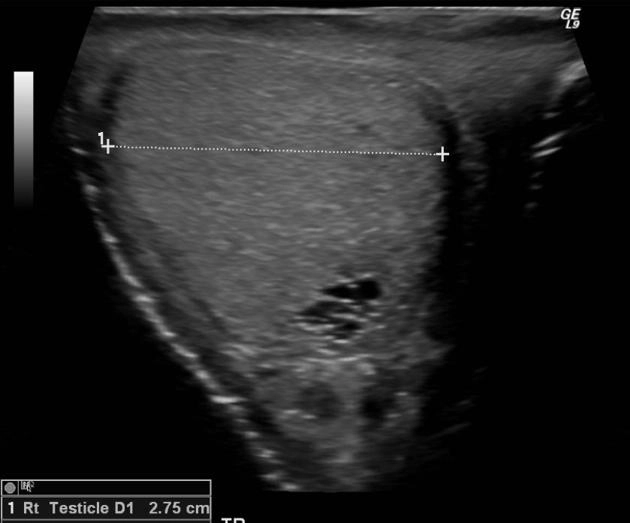

• Tổn thương một bên

Xoắn tinh hoàn (Testicular torsion)